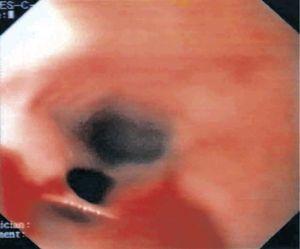

Fig. 2. Endoscopia digestiva alta en caso de perforación intramural espontánea del esófago en distintos tiempos.

Mujer de 42 años, que acude al servicio de urgencias al presentar un cuadro de dolor torácico retroesternal, no irradiado, de unas 12 h de evolución, acompañado de disfagia, odinofagia, sialorrea y regurgitación de contenido hemático-purulento, junto con fiebre de 39 oC. Entre los antecedentes personales destacaban episodios de disfagia ocasional desde la infancia, y tras múltiples pruebas complementarias (estudio baritado esofágico, endoscopia digestiva alta y manometría) se diagnosticó un trastorno motor esofágico inespecífico. Durante el ingreso se le realizaron diferentes pruebas: a) estudio baritado esofágico sin apreciar lesiones; b) endoscopia digestiva alta (figs. 1 y 2) con sedación profunda, donde se visualiza una estenosis parcial de la luz esofágica por compresión extrínseca a unos 20 cm de arcada dentaria, precedida de una laceración mucosa profunda en la pared esofágica con tractos fibrosos, del que rezuma sangre fresca en escasa cuantía; c) tomografía computarizada (TC) helicoidal torácica con y sin contraste intravenoso (fig. 3), donde se observa una formación tubular, que sigue casi todo el trayecto del esófago, con una cápsula bien definida que capta el contraste intensamente y que parece localizarse en el interior de la pared esofágica, con burbujas aéreas en su porción proximal, compatible con absceso esofágico intramural o quiste de duplicación esofágico complicado.